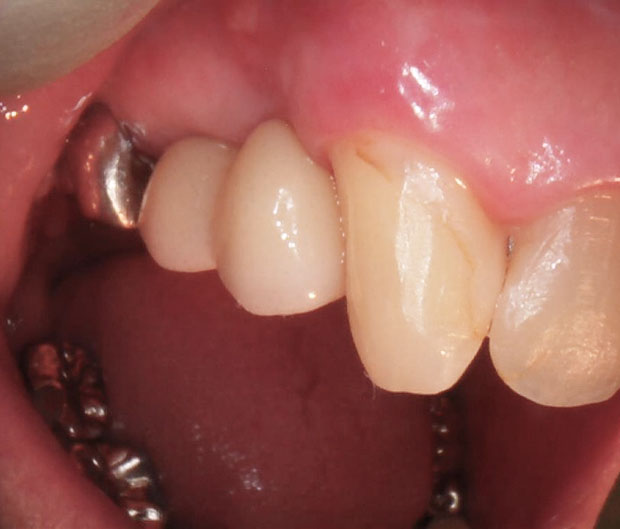

インプラントを入れた状態の写真とレントゲンです。

処置自体は20分ほどで終了し、術後の症状もほとんど出なかったとのことでした。

左上7番目にもむし歯があるのでそちらも治療します。

インプラントが骨とくっついたのを2ヶ月ほど待って、7番目と一緒に型取りをしました。

(7番目はむし歯を取って根の治療をしてます)